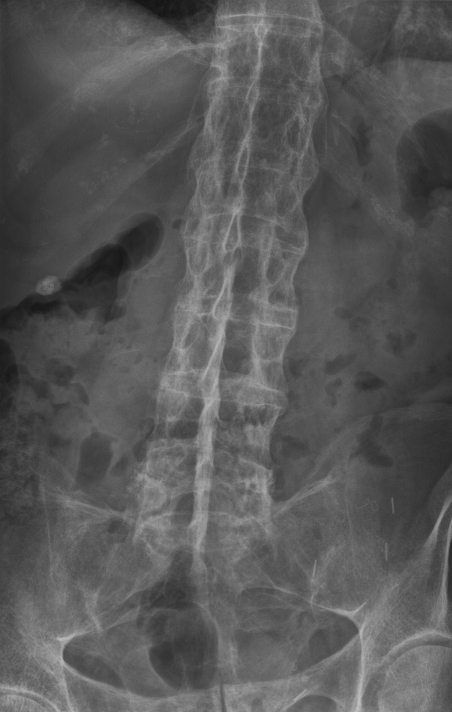

This is a chronic inflammatory disease that causes back pain and stiffness, primarily affecting the sacroiliac joints and spine.

“Following a consultation, physical assessment and X-rays, they found early fusion in my sacroiliac joint – a classic sign of ankylosing spondylitis, a form of axial spondyloarthritis.”

“With ankylosing spondylitis, inflammation gradually causes the spine to fuse, creating what is known as a ‘bamboo spine’.

“The spine’s normal gaps close due to chronic inflammation until it becomes one rigid stick.

“This makes it very fragile – if I get into an accident, my spine could easily break,” he explains.